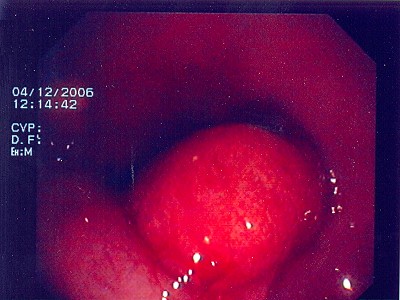

Großer Polyp des Dickdarmes